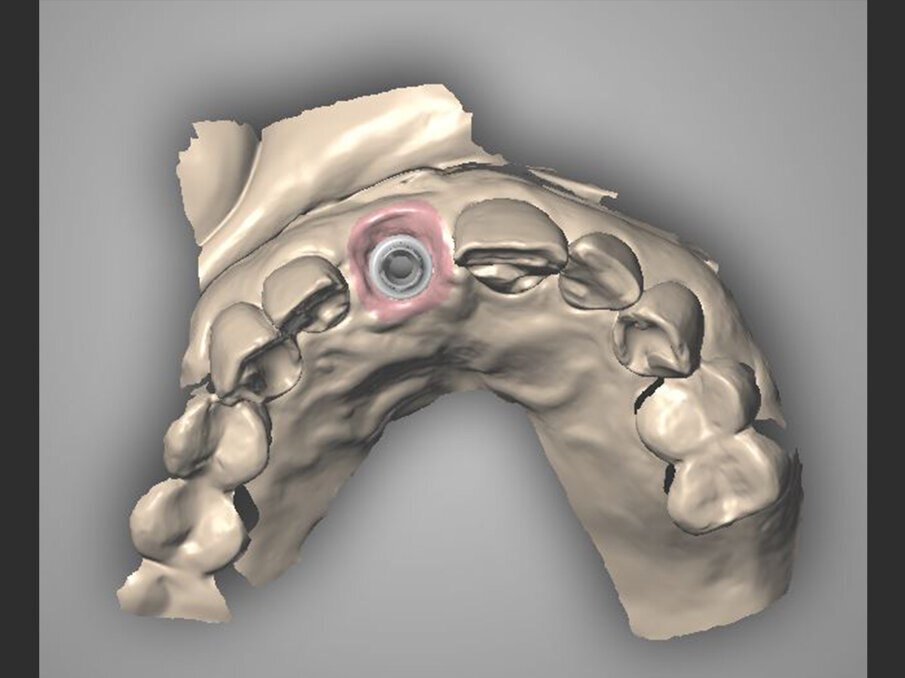

Il piano terapeutico stilato prevede l’estrazione dell’elemento compromesso e la sua sostituzione con un impianto post-estrattivo immediato a protesizzazione immediata. Ottenuto il consenso informato, la paziente viene sottoposta ad una seduta di igiene professionale e motivazione alle manovre di igiene domiciliare e viene eseguita un’impronta in alginato per poter realizzare una mascherina chirurgica termostampata, così da verificare l’asse d’inserimento implantare, ed un provvisorio in resina munito di alette di posizionamento.

Fig. 2b - CBCT iniziale con MyRay Hyperion X9 Pro.